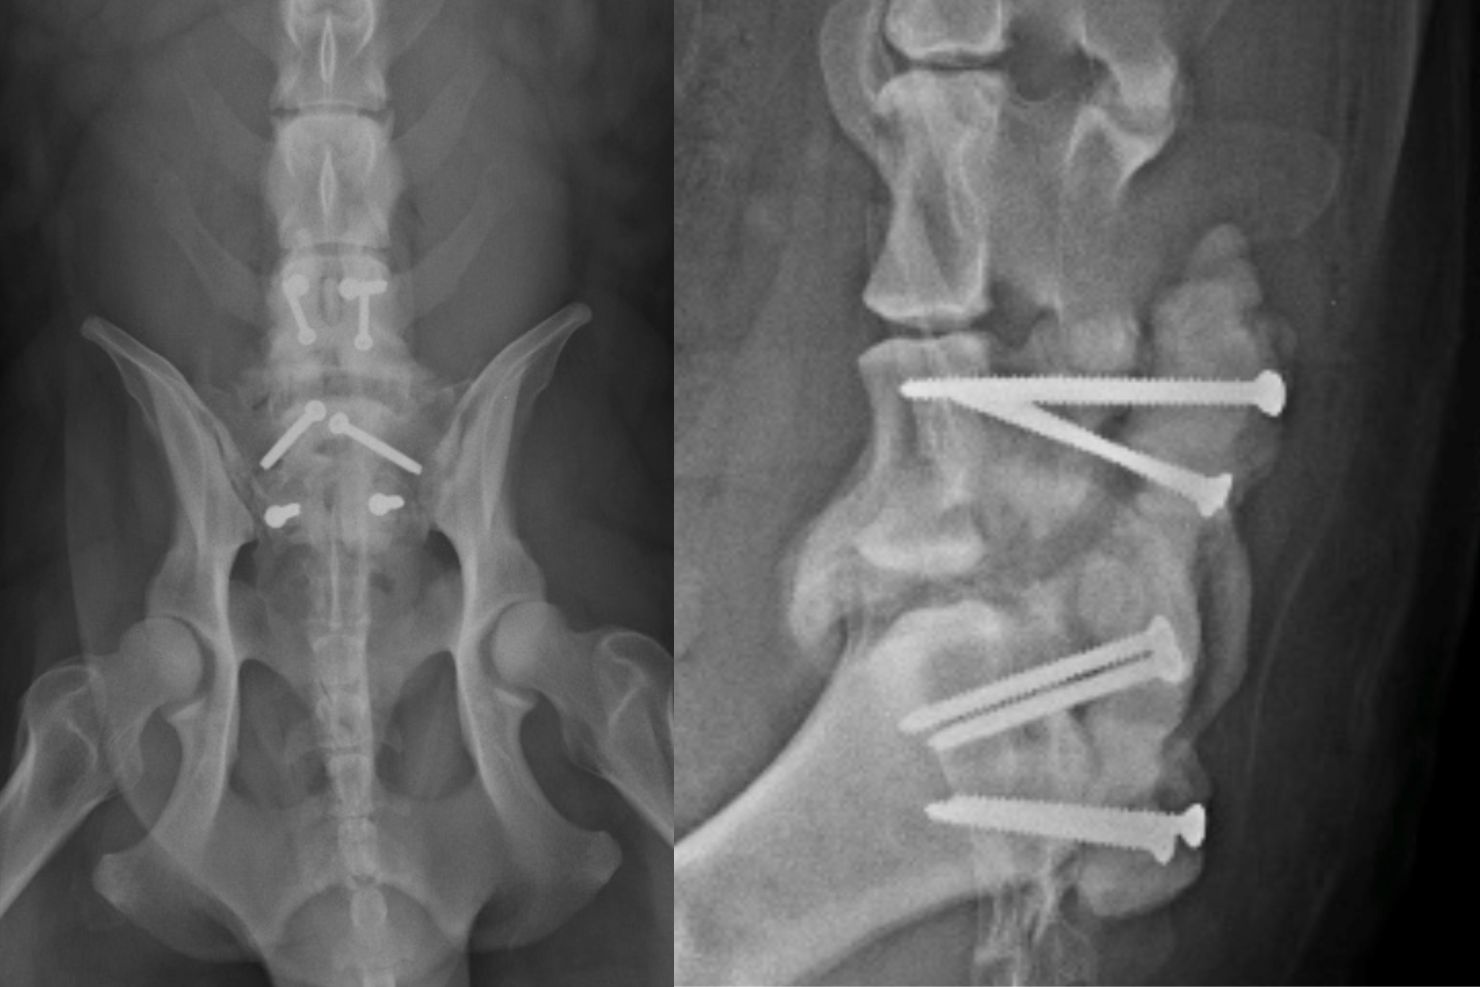

Die chirurgischen Lösungsansätze teilen sich in zwei Bereiche auf: Dekompression oder Stabilisation. Dekompression entlastet die komprimierte Struktur. Bei lateraler Nervenkompression kann zum Beispiel die bekannte Foraminotomie Erfolg bringen.

Es tut sich auf beiden Achsen der Therapie sehr viel. In der Schmerzbehandlung kommen neue Medikamente und Techniken zum Einsatz, die immer potenter werden und weniger Nebenwirkungen haben. In der Chirurgie wird immer mehr mit 3D-gedruckten Implantaten und Pedikelschrauben gearbeitet. Zusätzlich steigert sich die Erfahrung mit innerer Stabilisation, die in der Humanmedizin schon lange etabliert ist.